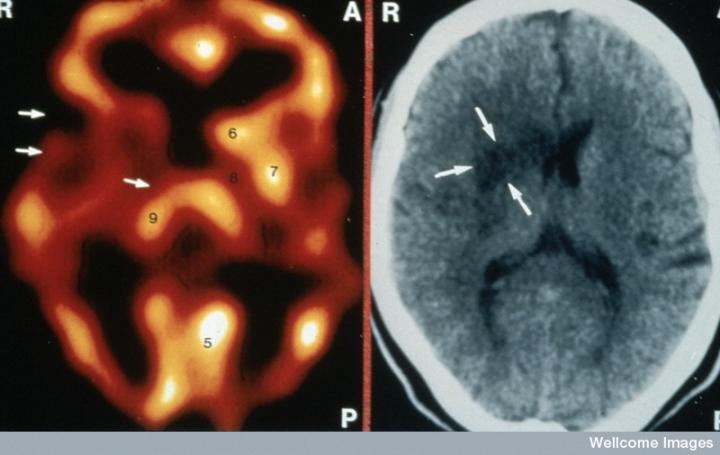

CT掃描的主圖顯示左側有一些中風損傷,由 Wellcome Images提供。Wellcome Photo Library提供的慢性中風的附加圖像 ,Wellcome Images,QL 從胚胎干細胞培養的神經元。Ying & A. Smith, Wellcome Images 和 Yirui Sun, Wellcome Images 移植的小鼠神經干細胞。